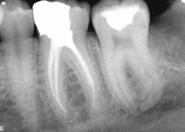

Radiografii

resorbtie osoasa

resorbtie osoasa accentuata